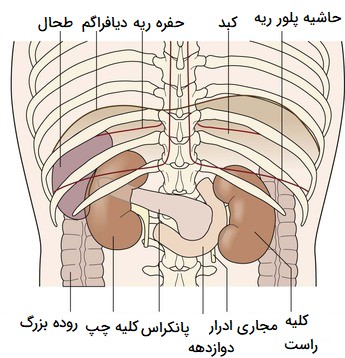

عکس کلیه در بدن. اگر پشت یا پهلوی شما آسیب ببیند مثل برخورد ضربه ممکن است فکر کنید که کلیه هایتان درد می کنند. مقدار و نسبت ترکیب این اخلاط در بدن هر شخصی و در اندامهای. کلیه گ رده ها1 از اندام های درونی بدن انسان به صورت یک جفت عضو لوبیایی شکل در طرفین ستون فقرات روی جدار پشتی شکم و بیرون از حفره صفاق قرار دارند. ک لیه ق لوه میز یا گ رده یکی از اندام های درونی بدن انسان و برخی دیگر از جانداران است.

کلسیم و فسفر که برای تشکلی استخوان لازمند کمک می کنند مواد. کلیه ها با تولید ادارد در دفع مواد زاید تعادل الکترولیتی تنظیم هورمونی تنظیم فشار خون و هوموستازگلوکز نقش دارند. آناتومی کلیه انسان در بدن انسان به این شکل است که کلیه ها دو عضو لوبیایی شکل در دستگاه ادراری بوده و به دفع مواد زائد به صورت ادرار کمک می کنند. یکی از مهم ترین وظایفی که کلیه ها در بدن بر عهده دارند پاک کردن و تصفیه خون از زباله هاست.